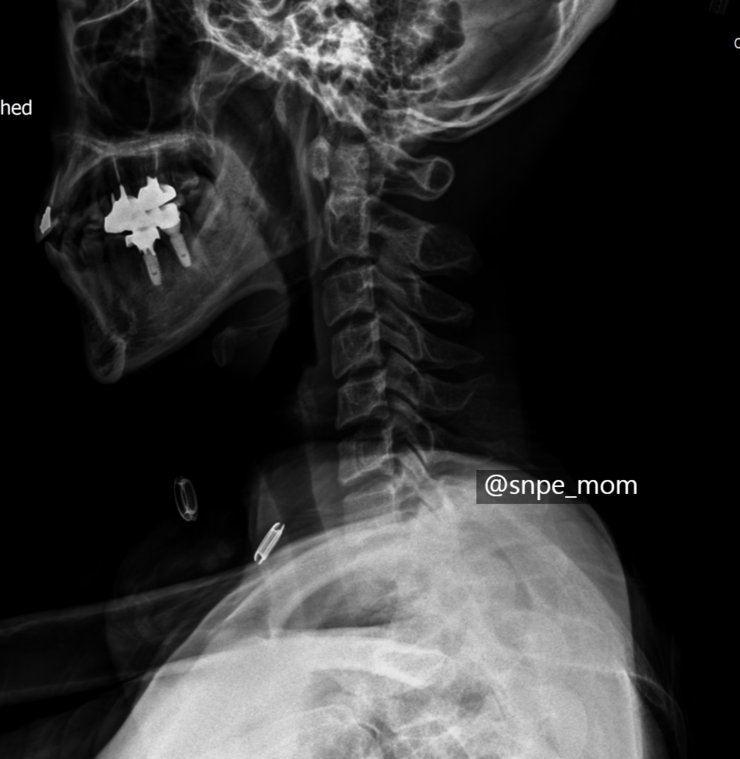

척추를 바로잡아야 건강이 보인다 51페이지에 바르지 못한 자세는 치아 건강에 영향을 준다는 ~ 내용이 너무 공감을 했습니다. 아래 사진은 제 엑스레이 사진인데요. 치아 부분에 햐얗게 된 부분이 ~ 다 치료한 이에요~;;  경추 1번이 보이기 위해서 입을 벌리고 찍으면 참 좋았을텐데, 아쉽지만 ~ 그래도 씌운 이의 압박이 보이시나요?ㅠ